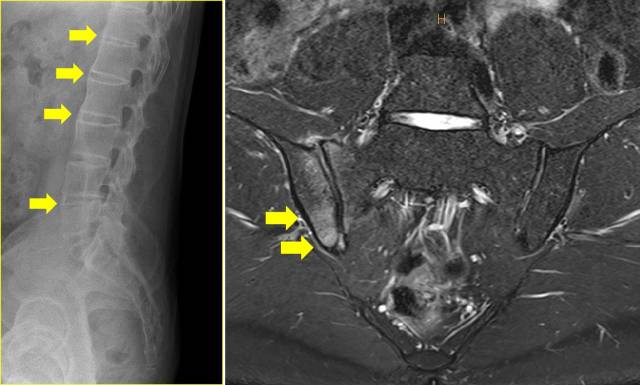

36세 남성 A씨는 몇 년 전부터 간헐적인 허리 통증을 경험했다. 그는 오랜 시간 앉아서 일하는 직업을 가진 탓에 피로가 누적된 것으로 여겼고 피곤할 때마다 진통소염제를 복용하는 데 그쳤다. 하지만 시간이 지나면서 통증이 점점 심해졌고 병원을 찾았을 땐 이미 대나무 척추 변형으로 진행된 상태였다(왼쪽 사진). 반면 27세 여성 B씨는 허리 통증이 세 달 넘게 이어지자 병원을 방문했다. 아침에 유독 통증이 심하고 움직이면 증상이 호전되는 특징을 보이자 단순한 근육통이 아닐 수도 있다는 생각이 들었다. 내원 당시 척추 엑스레이(오른쪽 사진)에서는 뼈의 강직이나 구조적 변화가 보이지 않았다. 반복적인 증상이 나타나 추가로 자가공명영상(MRI) 검사를 시행한 결과 천장관절의 염증이 확인돼 강직척추염으로 진단됐다. B씨는 조기 치료를 시작하고 꾸준한 운동을 병행하면서 질환의 진행을 막을 수 있었다. 강직척추염을 초기에 발견해 적극적으로 치료하면 진행을 억제할 수 있음을 보여주는 단적인 예다. 그러나 현실에서는 첫 번째 사례처럼 진단이 늦어져 병을 키우는 환자들이 많다.